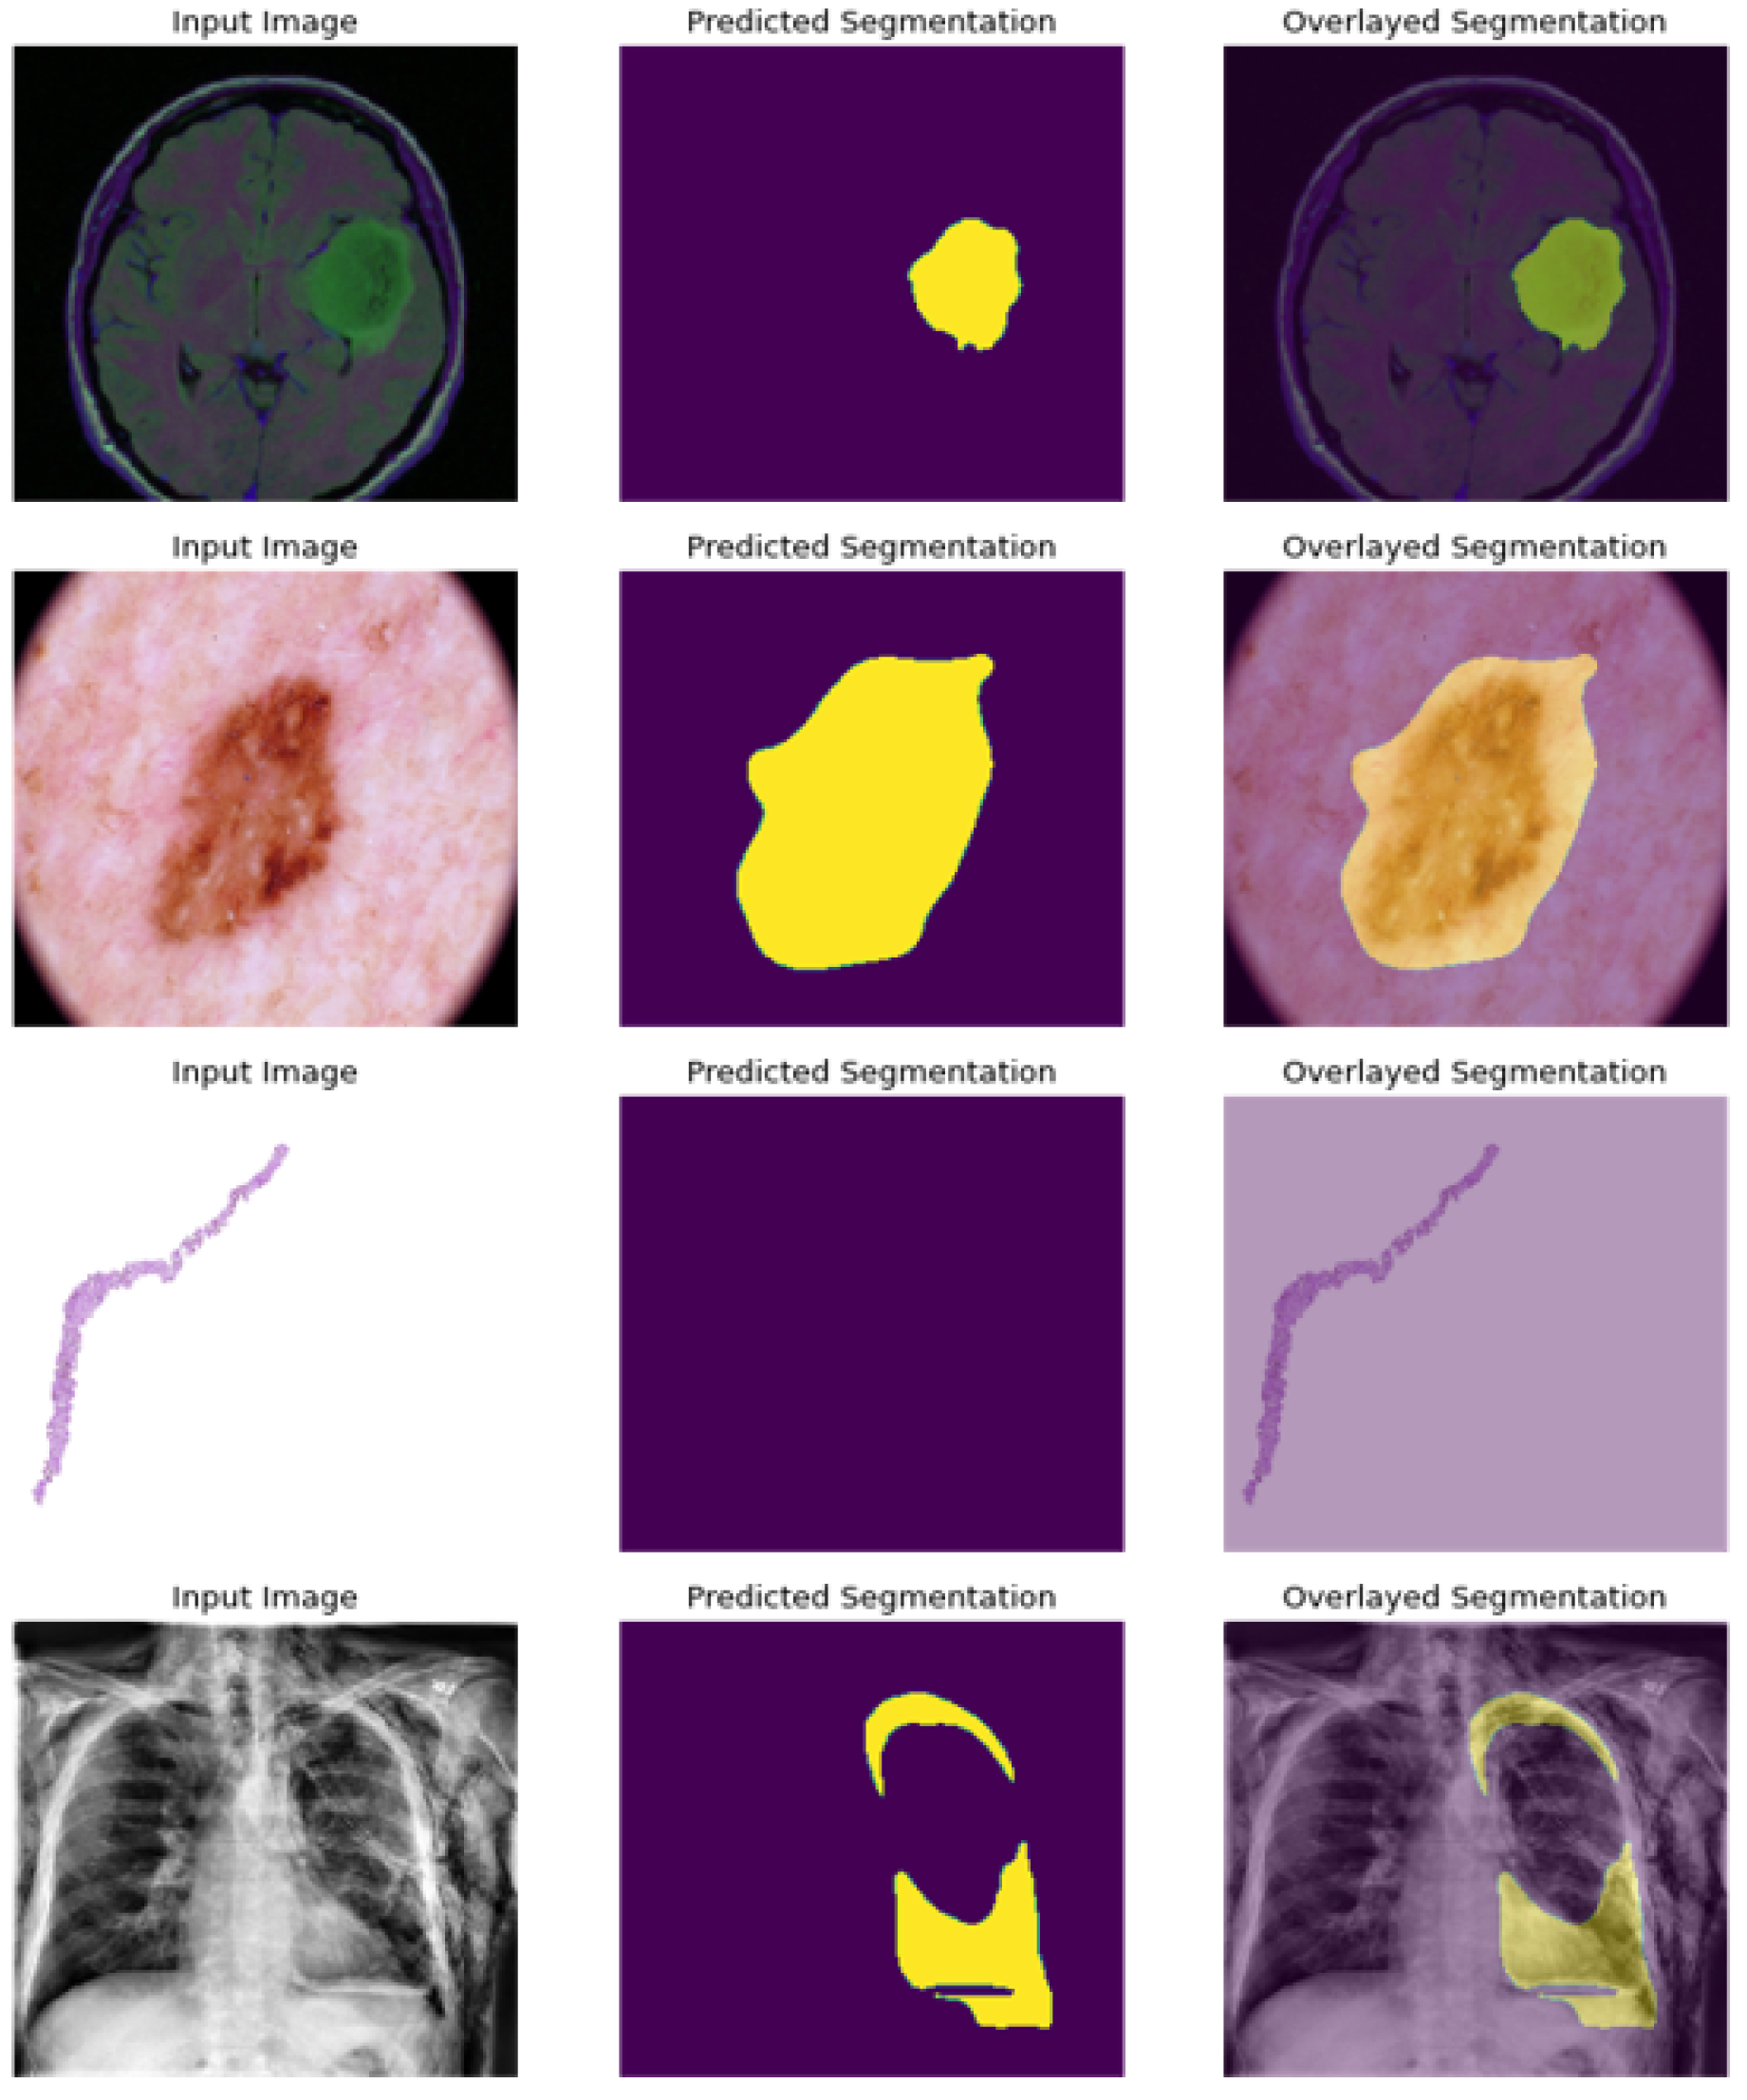

For the segmentation task, the multi-task model produced the best image segmentation results for the three cancer datasets, with a dice coefficient of 95%, 98%, 99% respectively against 80%, 96%, 85% for the single-task Attention-UNet model, also outperforming the Mask-RCNN model with 94%, 95%, 97% respectively for the Skin, Brain and Prostate cancer’s segmentation.The best dice coefficients for the three datasets were obtained with the MobilnetV2-based multi task model.

As presented in Figure 10; the model is able to precisely segment the region of disease in the scan image, and present an empty scan when classified as non cancerous as in the case of prostate image.

Figure 10. Segmentation results: Predicted masks overlay.